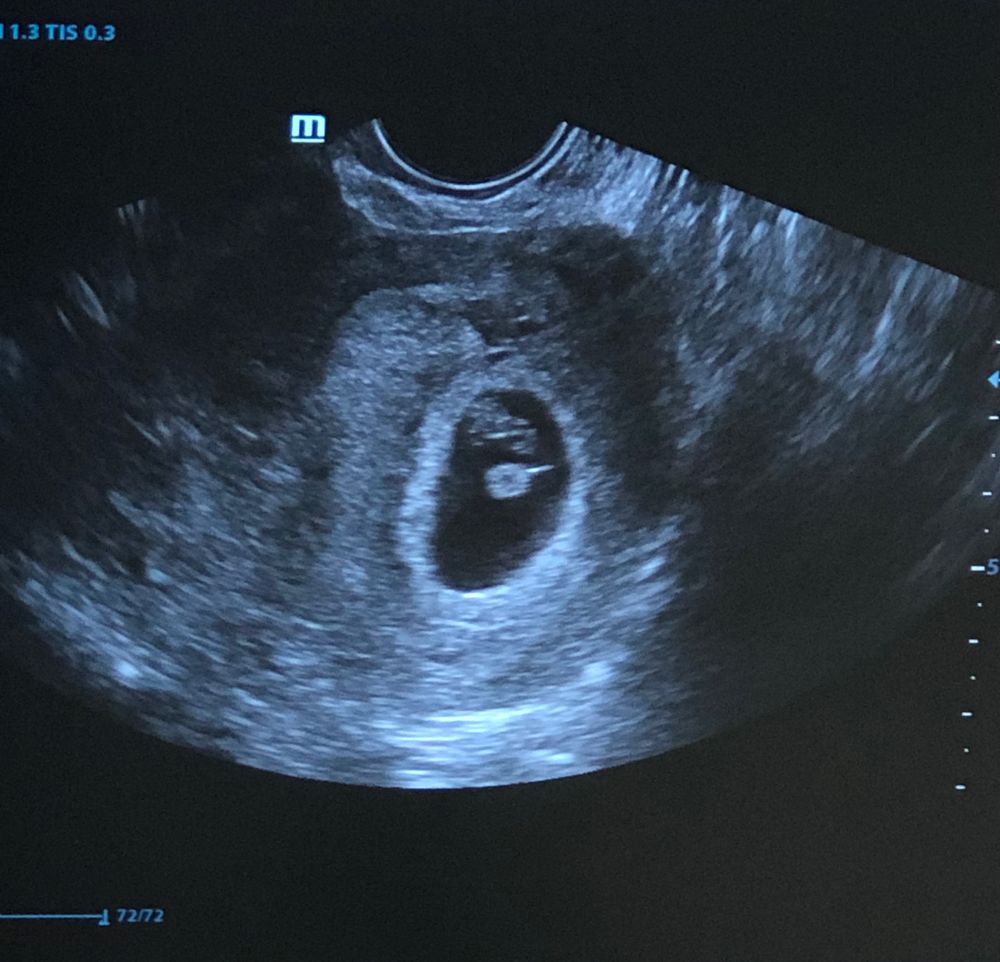

узи трансвагинальное, кого предложите?😬 узи в 7+2 недель

Надя, а как вы поняли ? Что нужно смотреть .. эмбриона прикрепление или желточный мешочек ? Потому что вот на фото они в разных сторонах

Dreams, пишут, что нужно смотреть на хорион (здесь его справа больше). Где находятся эмбрион и желточный мешок неважно.